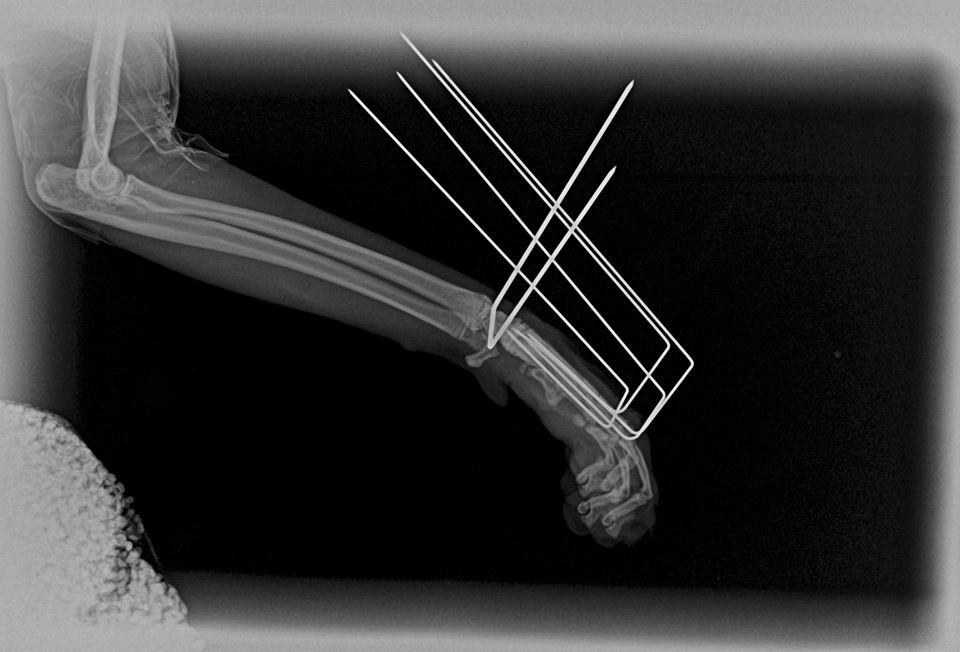

Tento černý kocourek spadl z 2. patra a zlomil si záprstí na jedné přední končetině. Konkrétně se jedná o sériovou frakturu všech metacarpálních kostí. Aby mohl zase běhat, bez operace se to neobešlo. Použili jsme externí skeletní fixaci tzv. „spider frame“, který poprvé použil Dr. Fitzpatrick, UK.